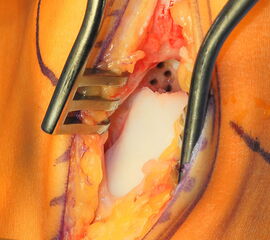

Operationstechnik (Fotos und Video)

Je nach Lage des Knorpeldefektes sind verschiedene Zugänge möglich. Ziel ist einen guten Zugang zum Defekt zu erreichen bei gleichzeitiger Vermeidung einer Innenknöchelosteotomie.

Die Darstellung der weiteren Operationstechnik erfolgt am Beispiel eines medialen Zugangs bei einer Osteochondrosis dissceans mit subchondraler Zyte der medialen Talusschulter (siehe MRT Abbildung 1).

Ist der umliegende Knorpel sehr dick oder liegt nur eine Defektzone mit 1-2 mm Tiefe vor, so kann die Kollagenmatrix auch gedoppelt in Sandwich-Technik implantiert werden. Beide Matrices werden mit der rauhen Oberfläche knochenseitig und der glatten Oberfläche gelenkseitig eingeklebt.